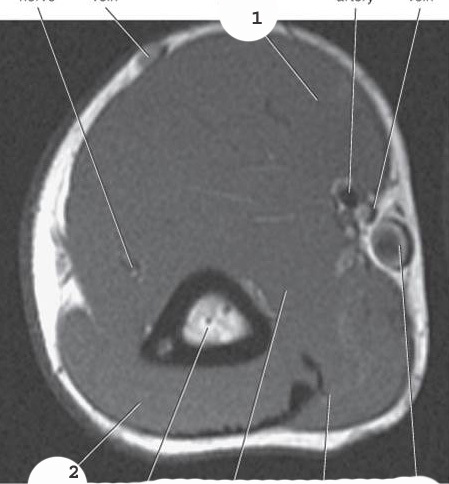

Aorta

2

Left common iliac artery

3

Left internal iliac artery

4

left external iliac artery

5

left femoral artery

1

popliteal artery